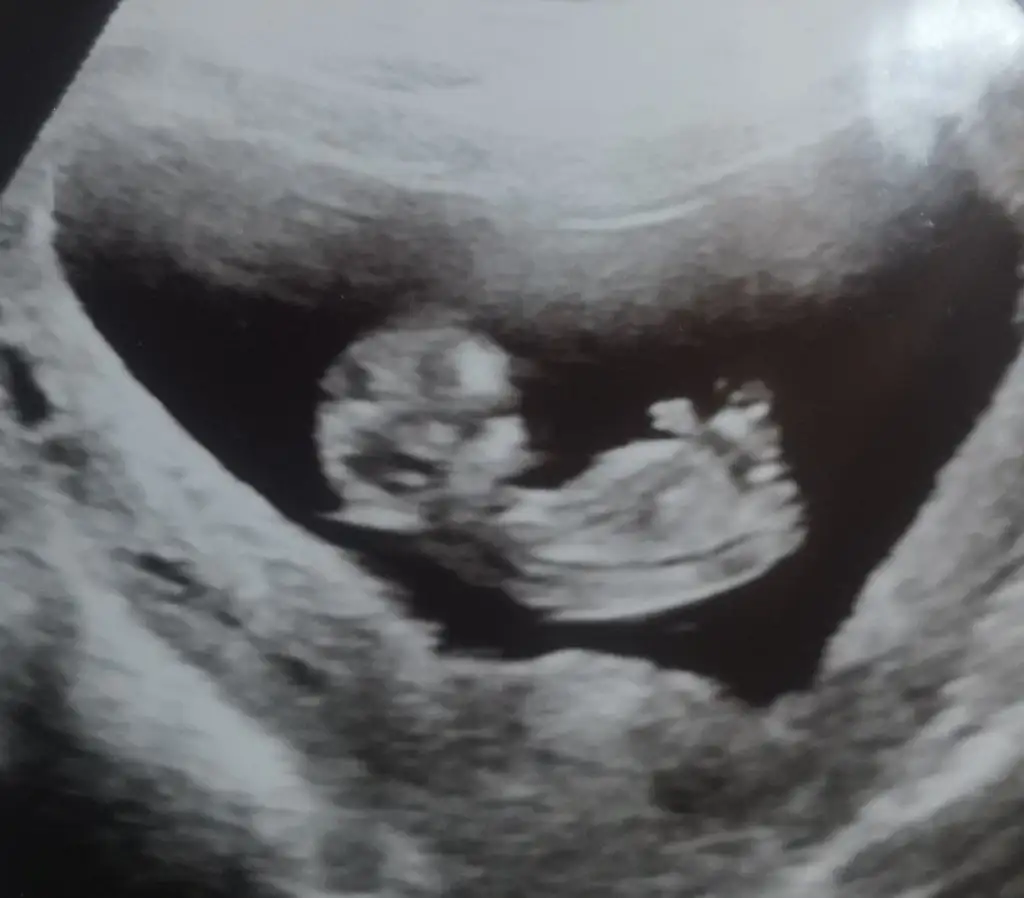

Merhaba, benim için de cinsiyet tahmini yapabilir misiniz? Bende çok merak ediyorum

Eklentiler

• IMG_20220927_231940.webp

19,1 KB · Görüntüleme: 102